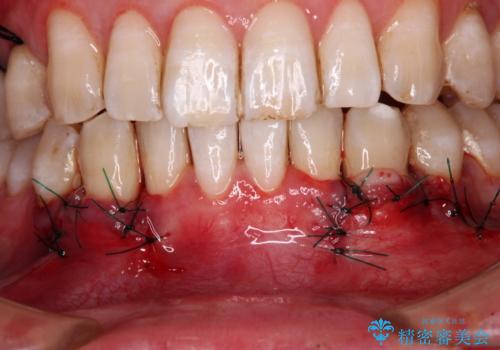

歯肉移植により根面被覆が達成されるとともに、歯肉が厚みを増したことで、今後の歯肉退縮リスクを軽減させることができました。

- 外科手術のため、術後に出血、痛みや腫れ、違和感を伴います